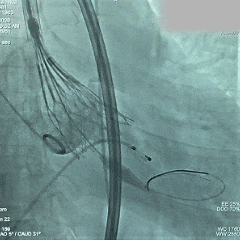

术中影像

根部造影:可见大量反流

导丝跨瓣

预弯型系统顺利跨过横位心

平齐窦底猪尾,0位定位

展开后造影,瓣膜位置偏深

回收后再次释放

第二次展开造影,瓣膜位置尚可,基本无漏